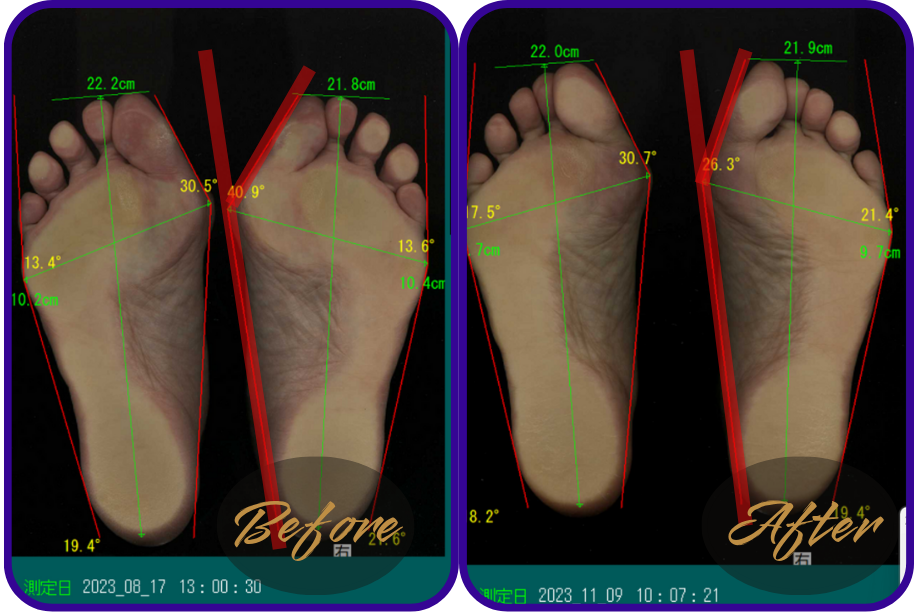

姿勢や歩き方の改善判断は、足裏の圧力画面や外反母趾の数値で出します。

ダイエットと同じで、体重やサイズを数値でみないとダイエットに成功したかわからないですものね。

↑39,5°あった外反母趾が27,7°まで改善。

↑足幅10,9㎝あったのが9,7㎝まで細くなった。

歩行整体に通われた患者様の足裏の様子をご紹介します。

※テーピングやゴムバンドなどは使用しておりません。整体と姿勢歩き方レッスンのみです。

↑50代女性

お悩み…足の付け根の痛み、膝の痛み、おしゃれな靴が履けない。

感想…「外反母趾が改善すると足の付け根と膝の痛みも消えました!」